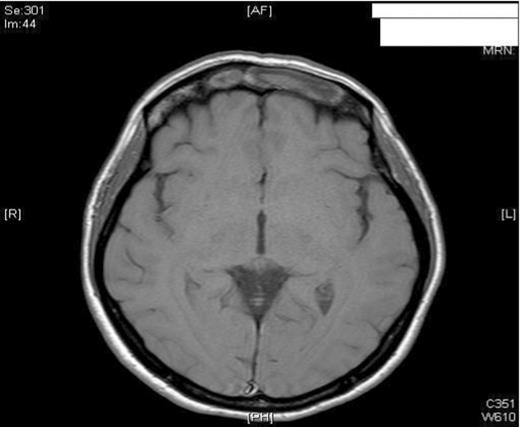

A 47-year old female smoker presented to the ENT department with worsening pain and progressive swelling to her left peri-orbital region and eyelid. On clinical examination the patient was acutely unwell. Rhinoscopy revealed mucopus draining from the left middle meatus. CT scanning revealed severe sinus disease in both frontal sinuses, with the left frontal sinus being expanded suggesting the presence of a mucocele (Figure 1). Both Frontonasal recesses and osteomeatal complexes were seen to be occupied by material bilaterally. Following Opthalmological review, she was managed initially with intravenous antibiotics and systemic steroids as well as intranasal steroids, decongestants and antimicrobial eye ointment. However, due to failure in resolution of symptoms, she was listed for surgical drainage of the mucocele using balloon sinuplasty.

MRI imaging (a) coronal (b) axial views post procedure revealing resolution of the mucocele and no intracranial or orbital complications (see figure 1).